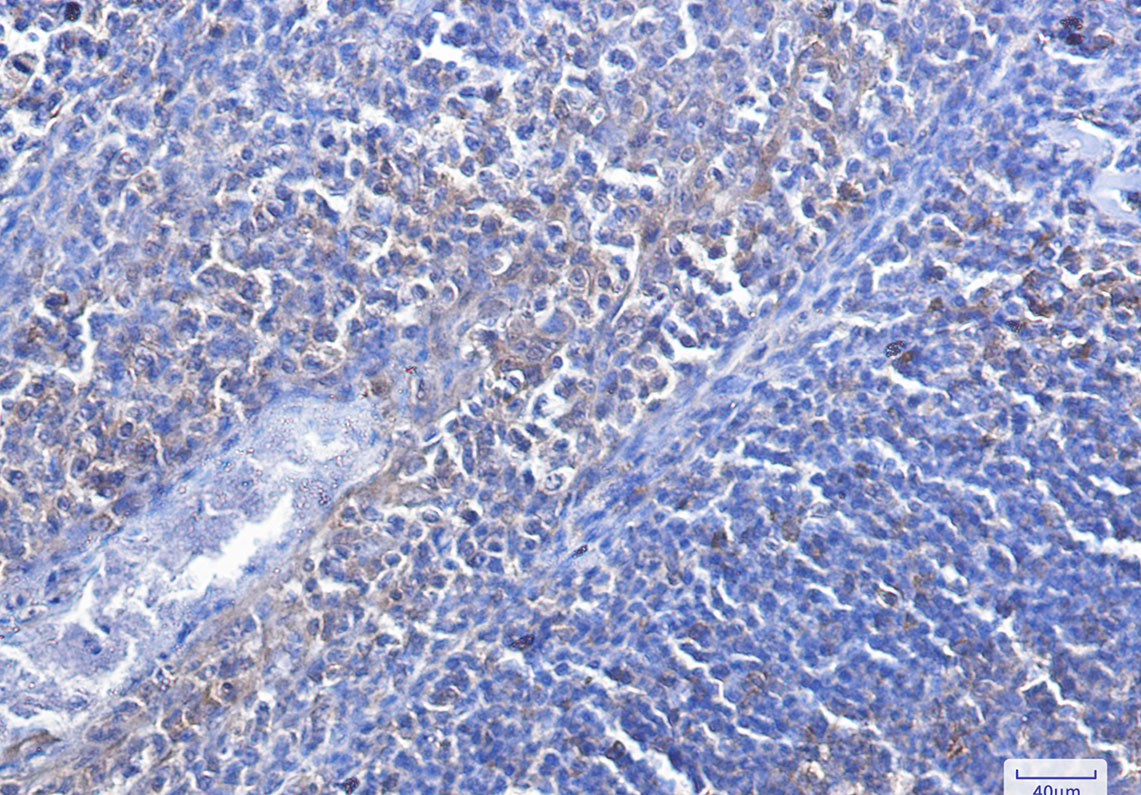

Caspase 3 Rabbit mAb

| Dilution | WB~~1:500-1:1000 IHC-P~~1:50~200 IP~~1:50-1:100 |